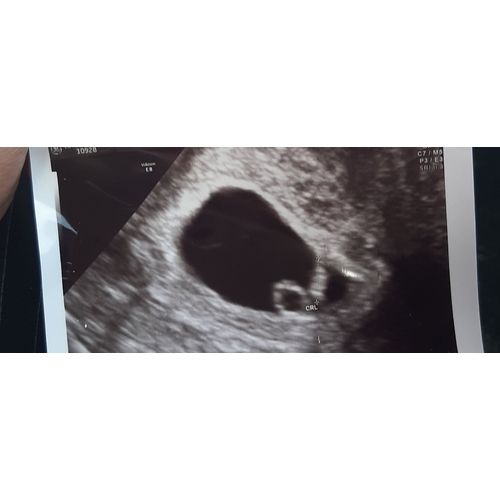

Uitwendig 11 weken en 4 dagen graag wie weet geslacht!

Deze kun je echt het beste plaatsen bij de Nub topic..

Ramzi theory is geschikt tot zo'n 9w..